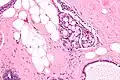

Micrograph of collagenous spherulosis with the characteristic histomorphology - intratubular eosinophilic material with a spoke-like arrangement. H&E stain.

Collagenous spherulosis is characterized by a tubular/cribriform architecture with intratubular eosinophilic material that classically is arranged like the spokes of a wheel ("radial spikes"). There is usually no mitotic activity, and two cells populations (epithelial & myoepithelial) are present, like in benign breast glands.

The lesions are typically small (less than 50 spherules per lesion, less than 100 micrometers in size) and may be multifocal.